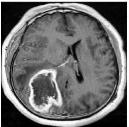

Machine learning has been widely adopted for medical image analysis in recent years given its promising performance in image segmentation and classification tasks. The success of machine learning, in particular supervised learning, depends on the availability of manually annotated datasets. For medical imaging applications, such annotated datasets are not easy to acquire, it takes a substantial amount of time and resource to curate an annotated medical image set. In this paper, we propose an efficient annotation framework for brain MR images that can suggest informative sample images for human experts to annotate. We evaluate the framework on two different brain image analysis tasks, namely brain tumour segmentation and whole brain segmentation. Experiments show that for brain tumour segmentation task on the BraTS 2019 dataset, training a segmentation model with only 7% suggestively annotated image samples can achieve a performance comparable to that of training on the full dataset. For whole brain segmentation on the MALC dataset, training with 42% suggestively annotated image samples can achieve a comparable performance to training on the full dataset. The proposed framework demonstrates a promising way to save manual annotation cost and improve data efficiency in medical imaging applications.

翻译:近年来,由于在图像分割和分类任务方面表现良好,医学图像分析广泛采用了机器学习。机器学习的成功,特别是监督学习的成功,取决于手动附加说明数据集的可用性。对于医疗成像应用来说,这种附加说明数据集不容易获得,需要大量的时间和资源来翻译附加说明的医学成像集。在本文件中,我们建议为大脑MR图像建立一个高效的注释框架,为人类专家提供信息性样图像,供人类专家作说明。我们评估了两种不同的大脑图像分析任务的框架,即脑肿瘤分割和整个大脑分割。实验显示,对于BRATS 2019数据集的脑肿瘤分割任务,培训一个只有7%的附加说明图像样本的分解模型,其性能与全数据集培训的性能相当。对于MALC数据集的整个大脑分割,用42%的附加说明性图像样本进行的培训,可以实现与全数据集培训的类似性能。拟议的框架展示了节省人工注解成本和提高医疗成像应用数据效率的有希望的方法。